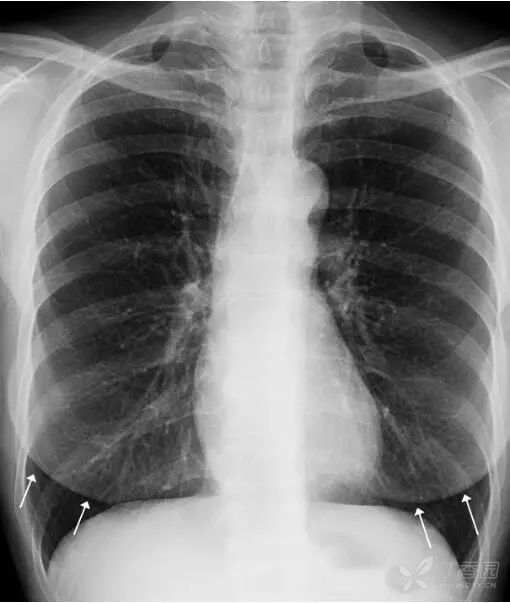

女性乳腺 女性乳腺相对胸部其他软组织较厚,因此在胸部正位X线平片上可以显示,通常重叠在两肺下野导致其密度增高,易被误认为肺内实变或肺内炎症。

上图女性乳腺影重叠在两肺下野,导致两肺下野对称性密度增高,乳腺形成投影的下缘(白色箭头)是清晰锐利的并且呈半圆形,常向外与腋部皮肤连续。没有乳腺重叠的两肺肋膈角区域更透亮。

鉴别:①两侧乳腺常规比较对称,所以在正位胸片上,乳腺重叠导致的两肺下野的密度增高也是比较对称的。而两肺下野均有病变且有分布比较对称的病理情况是比较少见的。②乳腺影的下缘清晰锐利且呈半圆形,向外与腋部皮肤连续。而肺内的病变不会延续到两肺以外。